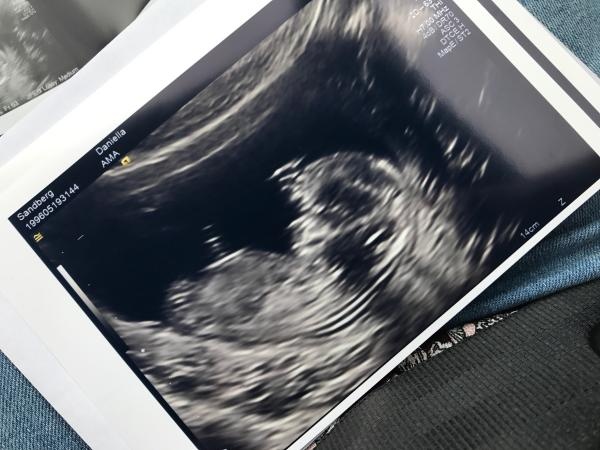

Någon som vill gissa kön på min bebis? Hade varit så kul att spekulera lite! Jag tror att derby är en pojke, fästmannen tror flicka ????